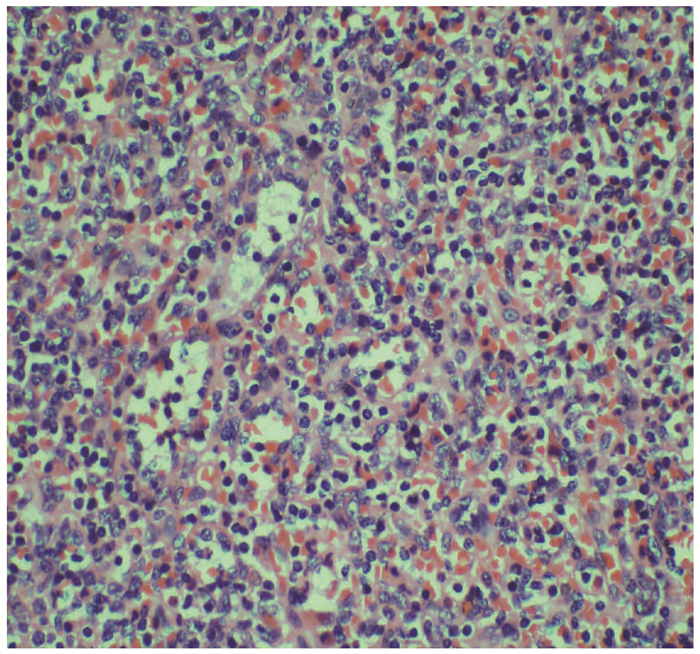

华东沿海地区多中心40例胰腺肿瘤患者基因组图谱分析

王晶, 谭斌, 赵志杰, 仲灏辰, 曲林林

2022, 38(2): 409-414. DOI: 10.3969/j.issn.1001-5256.2022.02.028

摘要(1257) HTML (372) PDF (3577KB)(64)

摘要:

目的  探讨我国华东沿海地区胰腺癌患者的基因突变情况,为个体化治疗提供依据。  方法  选取2017年1月—2019年6月在青岛大学附属医院、青岛市立医院、烟台山医院、烟台中法友好医院收治并经手术治疗后诊断为胰腺恶性肿瘤的患者40例。采用下一代测序技术检测肿瘤组织和体细胞中的基因突变。绘制基因突变图谱,分析基因组改变。计数资料组间比较采用χ2检验或Fisher精确检验。采用Kaplan-Meier法绘制生存曲线,组间比较采用log-rank检验。  结果  40例患者中胰腺导管腺癌34例(85.0%),胰腺实性假乳头状肿瘤3例(7.5%),胰腺神经内分泌肿瘤1例(2.5%),分型不清2例(5.0%)。KRAS(80.0%,32/40)、TP53(70.0%,28/40)、CDKN2A(32.5%,13/40)、SMAD4(17.5%,7/40)和AKT2(17.5%,7/40)是最常见的突变。5种常见基因突变的生存时间差异均无统计学意义(P值均>0.05)。  结论  下一代测序技术能够提供全面、准确的基因组改变信息,可为胰腺癌的诊断和精确治疗提供新的潜在生物标志物。通过对突变基因进行分析,从而为胰腺癌的个体化治疗奠定基础。